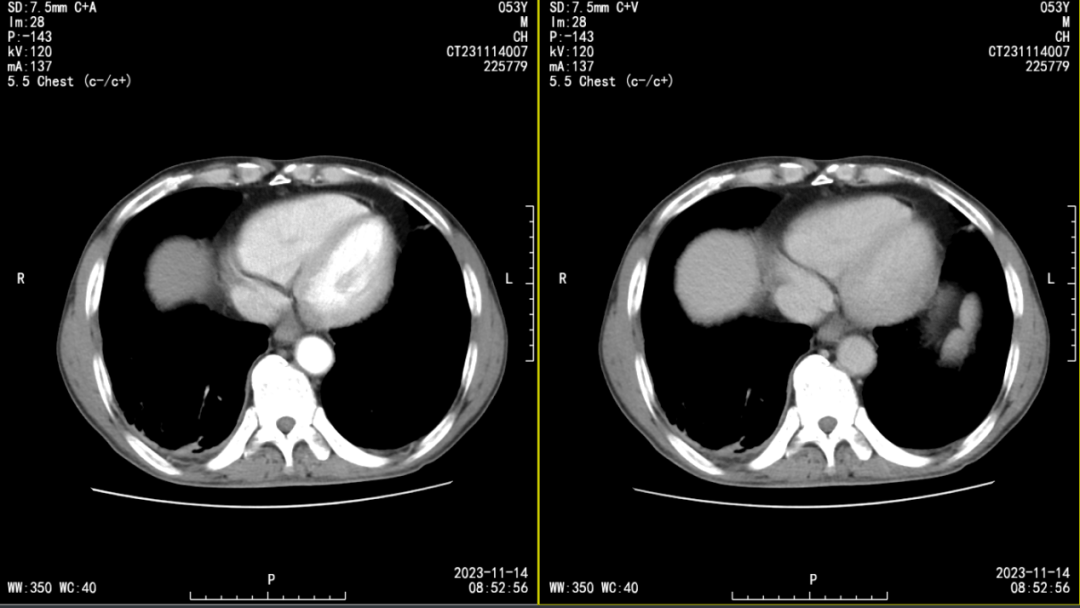

血源性多发性肺脓肿

图片尺寸823x516